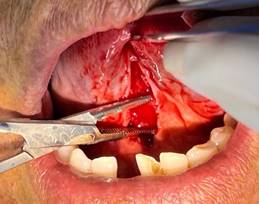

· Diéresis: Se sujetó la lengua con la ayuda de una pinza Adson con dientes, después se utilizó el electrobisturí realizando cortes lineales verticales o ligeramente convergentes hacia apical. (Figura 4)

Figura 4. Diéresis.

Elaboración: Los autores.